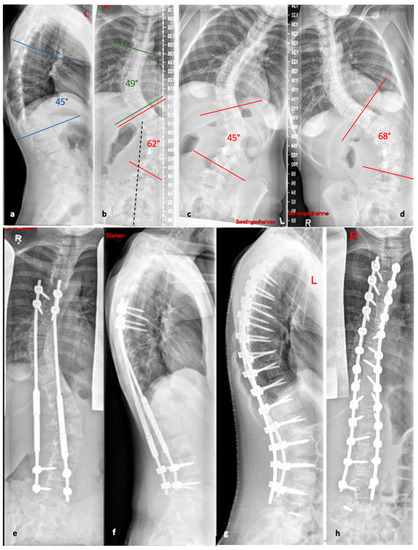

Figure 5. (a,b). Initial radiographs of a patient with adolescent idiopathic scoliosis. (c,d). Bending radiographs. (e,f). Postoperative image displaying implanted magnetically controlled growing rods as a dual rod system. (g,h). The patient was treated with a spondylodesis upon the completion of growth to maintain correction success (Reprinted with permission [10]).

To avoid the regular surgical lengthening procedure, MCGRs were developed and approved for the treatment of EOS in Europe in 2009. MCGRs are telescopically extendable distraction rods. They can be distracted non-invasively, on an outpatient basis, by externally magnetically controlled lengthening using electromagnets. Figure 5 illustrates the progression of treatment for a patient with AIS, starting from initial diagnosis, through the bending radiographs, to the postoperative phase with implanted MCGR, and finally, the maintenance phase involving spondylodesis.

3.5.4. Magnetically Controlled Growing Rods